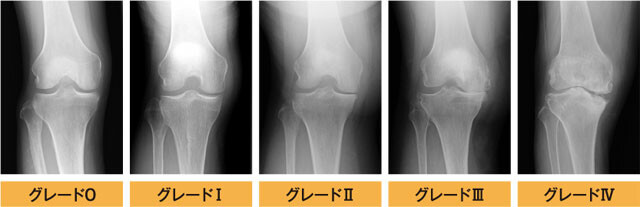

変形性膝関節症は

kellgren-Lawrenceの分類でグレード0〜Ⅳの5段階で

変形の進行度が分類されます。

グレード0:特に異常が見られない

グレード1:関節と関節の隙間が狭くなり骨棘(こつきょく)の発現がみられます

グレード2:骨棘(こつきょく)がはっきりと現れ関節と関節の隙間が狭くなっている

グレード3:複数の骨棘(こつきょく)が形成され軟骨がすり減り硬化している状態

グレード4:著しく骨棘(こつきょく)が発現し関節と関節の隙間が狭小し軟骨が硬化